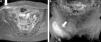

Desgarro de los músculos glúteo menor y medio. Las secuencias en ponderación STIR, planos (a) axial y (b) coronal, detectan la rotura parcial a nivel de la unión miotendinosa distal de ambos músculos. Se observa bursitis intertrocantérea y edema del vientre muscular a predominio del glúteo menor (flechas).

Desgarro del piriforme o piramidal de la pelvis (flecha interna) y glúteo medio (flecha externa) izquierdos. La secuencia ponderada en STIR, plano axial, registra una rotura fascicular de ambos grupos musculares, con marcados signos de edema de partes blandas. La RM, por su amplio campo visual, permite reconocer desgarros de grupos musculares adyacentes de localización profunda.